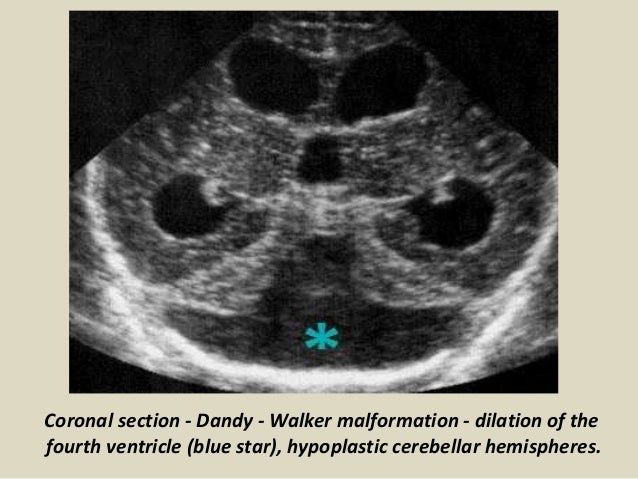

30. 30. Coronal section - Dandy - Walker malformation - dilation of the fourth ventricle (blue star), hypoplastic cerebellar hemispheres.